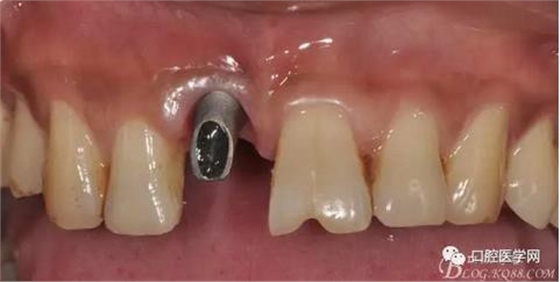

圖9 三個(gè)月后袖口形成正位照

圖10 三個(gè)月后袖口形成頜面照